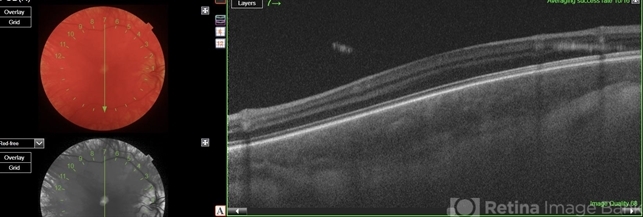

- OCT image of right eye showing foveal hypoplasia